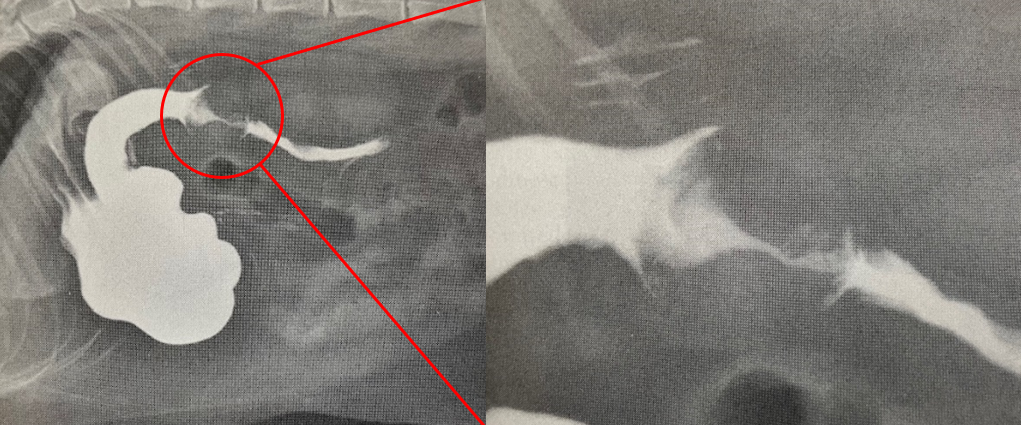

図3. 食道の造影前(左)およびバリウム造影実施後(右)のX線画像。

機械的に閉塞している場合はその異物や腫瘍などの周りを避けるように造影剤が染まるために鑑別可能(造影が起こらない箇所を「造影欠損」部といいます)、また時間経過毎にX線撮影を行う事で機能的に動きが遅くなっている状態(排出遅延)の鑑別も可能です。

図4. バリウム検査で造影欠損しているX線画像(ゴムボール)。